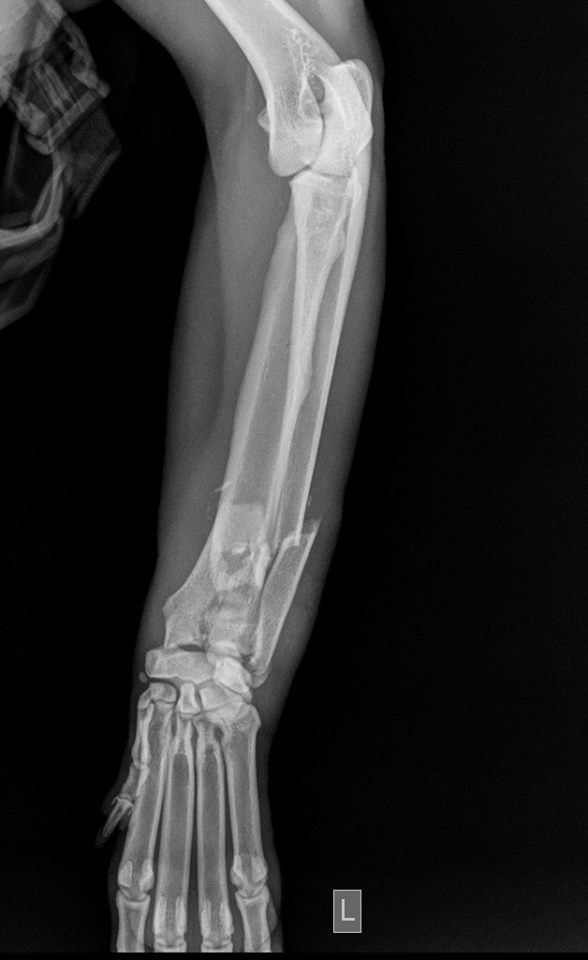

Η κα Μακρή δημοσίευσε σήμερα στο facebook την γνωμάτευση του κτηνιάτρου σχετικά με την εξέλιξη της υγείας του ζώου. Σε αυτή αναφέρεται ότι: «Ο σκύλος έφερε συντριπτικά ενδοαρθρικά κατάγματα με μετατόπιση στο κάτω τρίτο του αριστερού αντιβραχίου και στο κάτω τρίτο του αριστερού μηριαίου. Ολοκληρώθηκε με επιτυχία η πρώτη χειρουργική επέμβαση που αφορούσε την ανάταξη και οστεοσύνθεση του αριστερού αντιβραχίου. Λόγω της σοβαρότητας του κατάγματος η διάρκεια της χειρουργικής επέμβασης ήταν 4 ώρες και 25 λεπτά και ο σκύλος ανένηψε φυσιολογικά».